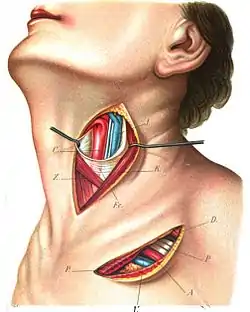

Arteria thyreoidea superior

Arteria thyreoidea superior (også kaldt øvre skjoldbruskkirtelarterie) er en arterie i halsen. Grenene af den øvre skjoldbruskkirtelarterie forsyner skjoldbruskkirtlen.

| Kilde | external carotid artery |

Hyoid artery Sternocleidomastoid artery Superior laryngeal artery Cricothyroid artery |

| Vene | superior thyroid vein |

| Forsyner | thyroid |